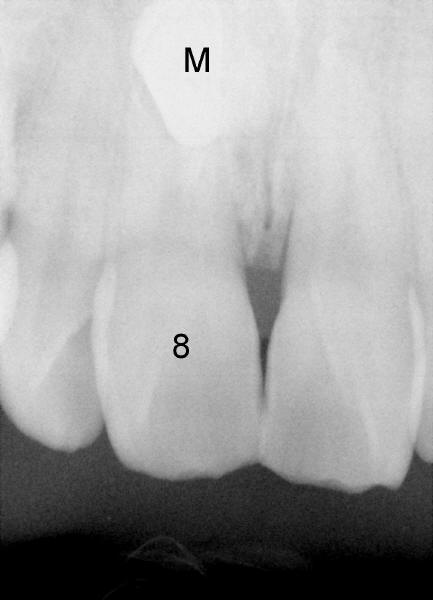

When a 39-year-old man presents for new patient exam and possible orthodontic treatment, PA shows a mesiodens (M) associated with #8, return to main article

Xin Wei, DDS, PhD, MS 1st edition 12/16/2011, last revision 12/17/2011